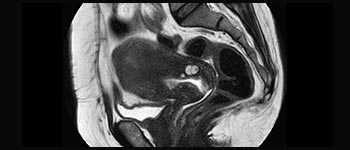

Enhanced diagnostic confidence in neuro oncology

Find the right clinical applications for your needs